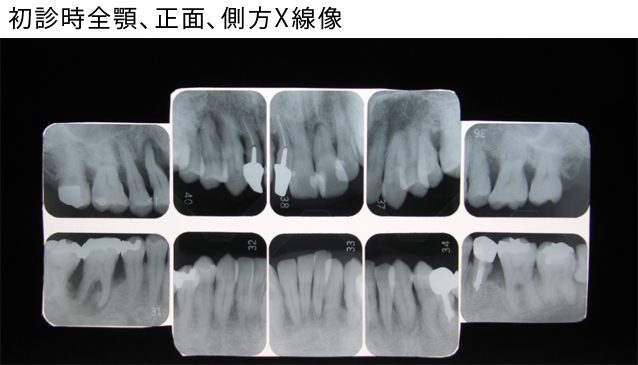

- レントゲン写真や検査等の資料を作成、確認し歯周病か否かを診断致します。